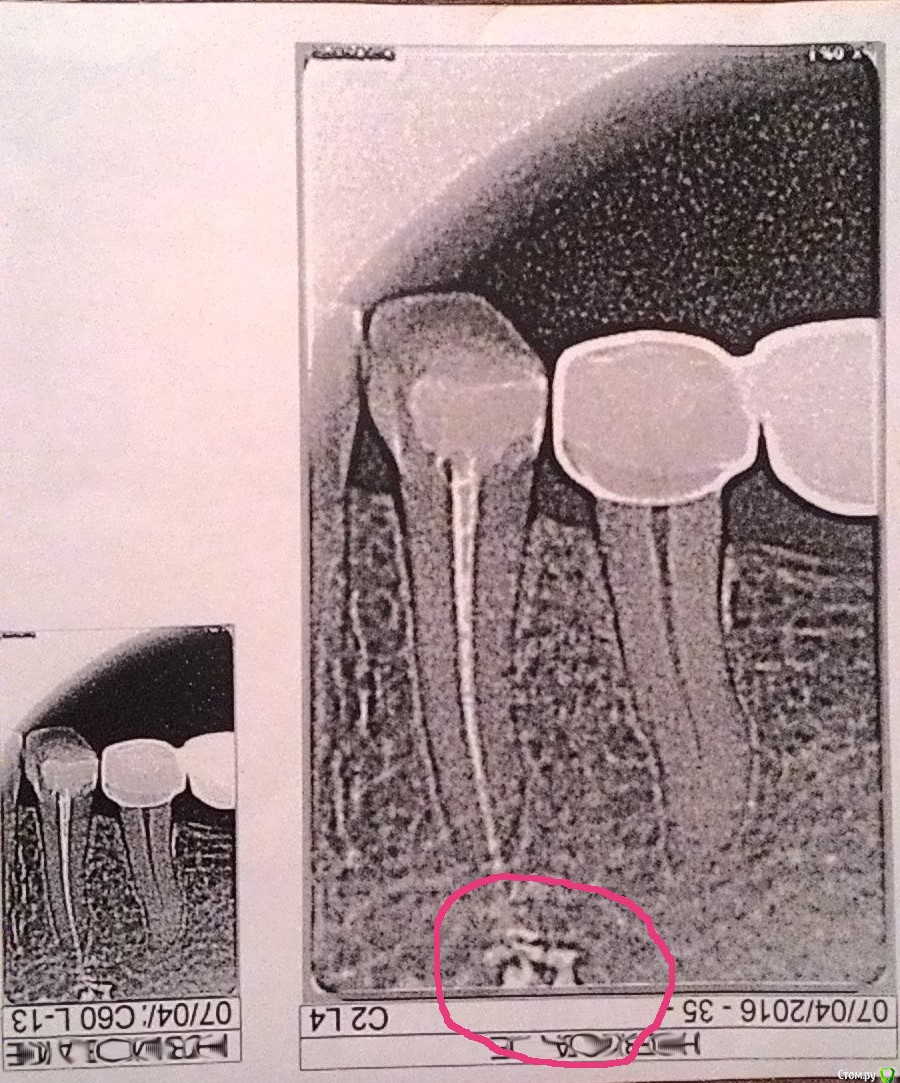

nowoleg Опубликовано 28 апреля, 2016 Поделиться Опубликовано 28 апреля, 2016 После удаления нерва и чистки каналов на протяжении месяца болит зуб. Снимок прикрепил.Врач сказал может зуб болеть около 6 месяцев и назначил электрофорез с преднизолоном, а в аптеке данного препрата уже нет.Хотелось бы узнает и менения других врачей. Каковы последствия? Нужно ли удалять зуб? Ссылка на комментарий

___49___ Опубликовано 29 апреля, 2016 Поделиться Опубликовано 29 апреля, 2016 (изменено) последствия различны - зависит от локализации и типа материала ,который выведен за пределы корня, соответственно последствия также различны . зная тип материала и имея КТ данного сегмента , планировать возможные решения сложившейся ситуации будет проще . ( и на форуме заочно , мы можем только подсказать , осветить вам возможные варианты, но не в коем случае не назначить лечения и т.д. так как отсутствие возможности очного осмотра, ограничивает нас в объективности) Изменено 29 апреля, 2016 пользователем ___49___ 2 Ссылка на комментарий